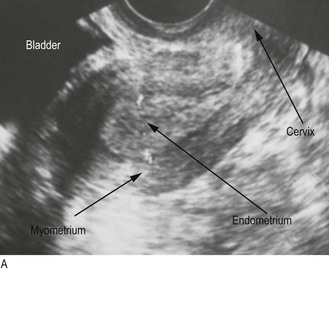

Pear-shaped, about 6–8 cm long, 4–6 cm wide and stabilised by the broad ligament, the uterus lies between the bladder and rectum and consists of muscular myometrium surrounding a cavity lined by endometrium (Figs 10.17 and 10.18). Ovarian hormones stimulate the endometrium to proliferate; secretion and breakdown (menstruation) follow.